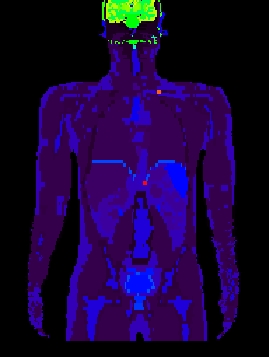

Figure 2. left: coronal slice through the Zubal phantom with inserted lesions (red points). Middle: simulated PET image corresponding to the Zubal model. Right: superimposed label model and PET simulated data.